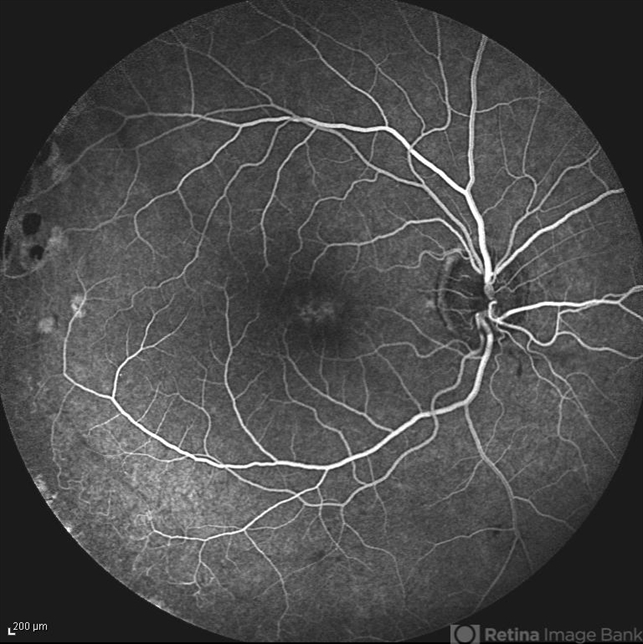

- x-linked retinoschisis (XLRS), foveal schisis

- Mid venous phase FA of the right eye of a 35-year-old man with x-linked retinoschisis. Please notice the foveal schisis.